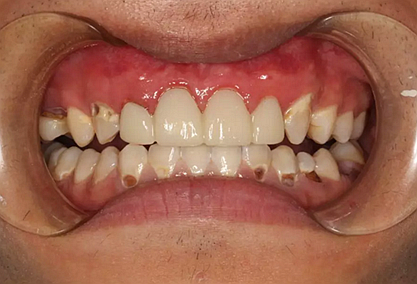

我們的主人今年才25歲,可卻從很小的時候就嗜好喝可樂等碳酸飲料,幾年下來,讓我們兄弟姐妹們整天浸在碳酸里受這蝕骨之痛,原本皎潔的外貌如今早己經(jīng)是腐蝕不堪、丑陋無比,更有甚者,一些兄弟姐妹們已經(jīng)病入膏肓,被病痛折磨奄奄一息。

下面是醫(yī)生眼中和ct下的我們

一身病痛啊

牙結(jié)石、牙齦炎癥、牙體殘缺、慢性牙髓炎、蛀牙......